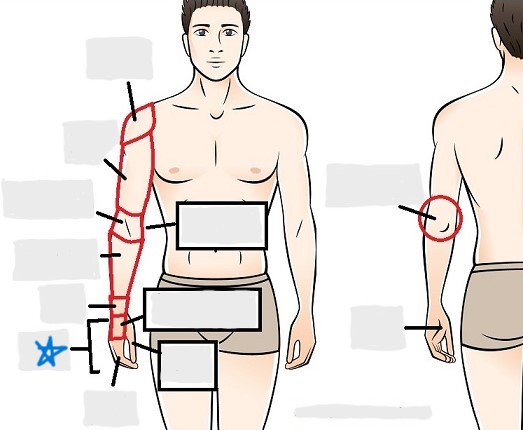

axial

appendicular

acromial

brachial

antecubital

olecranal

antebrachial

carpal

manus

coxal